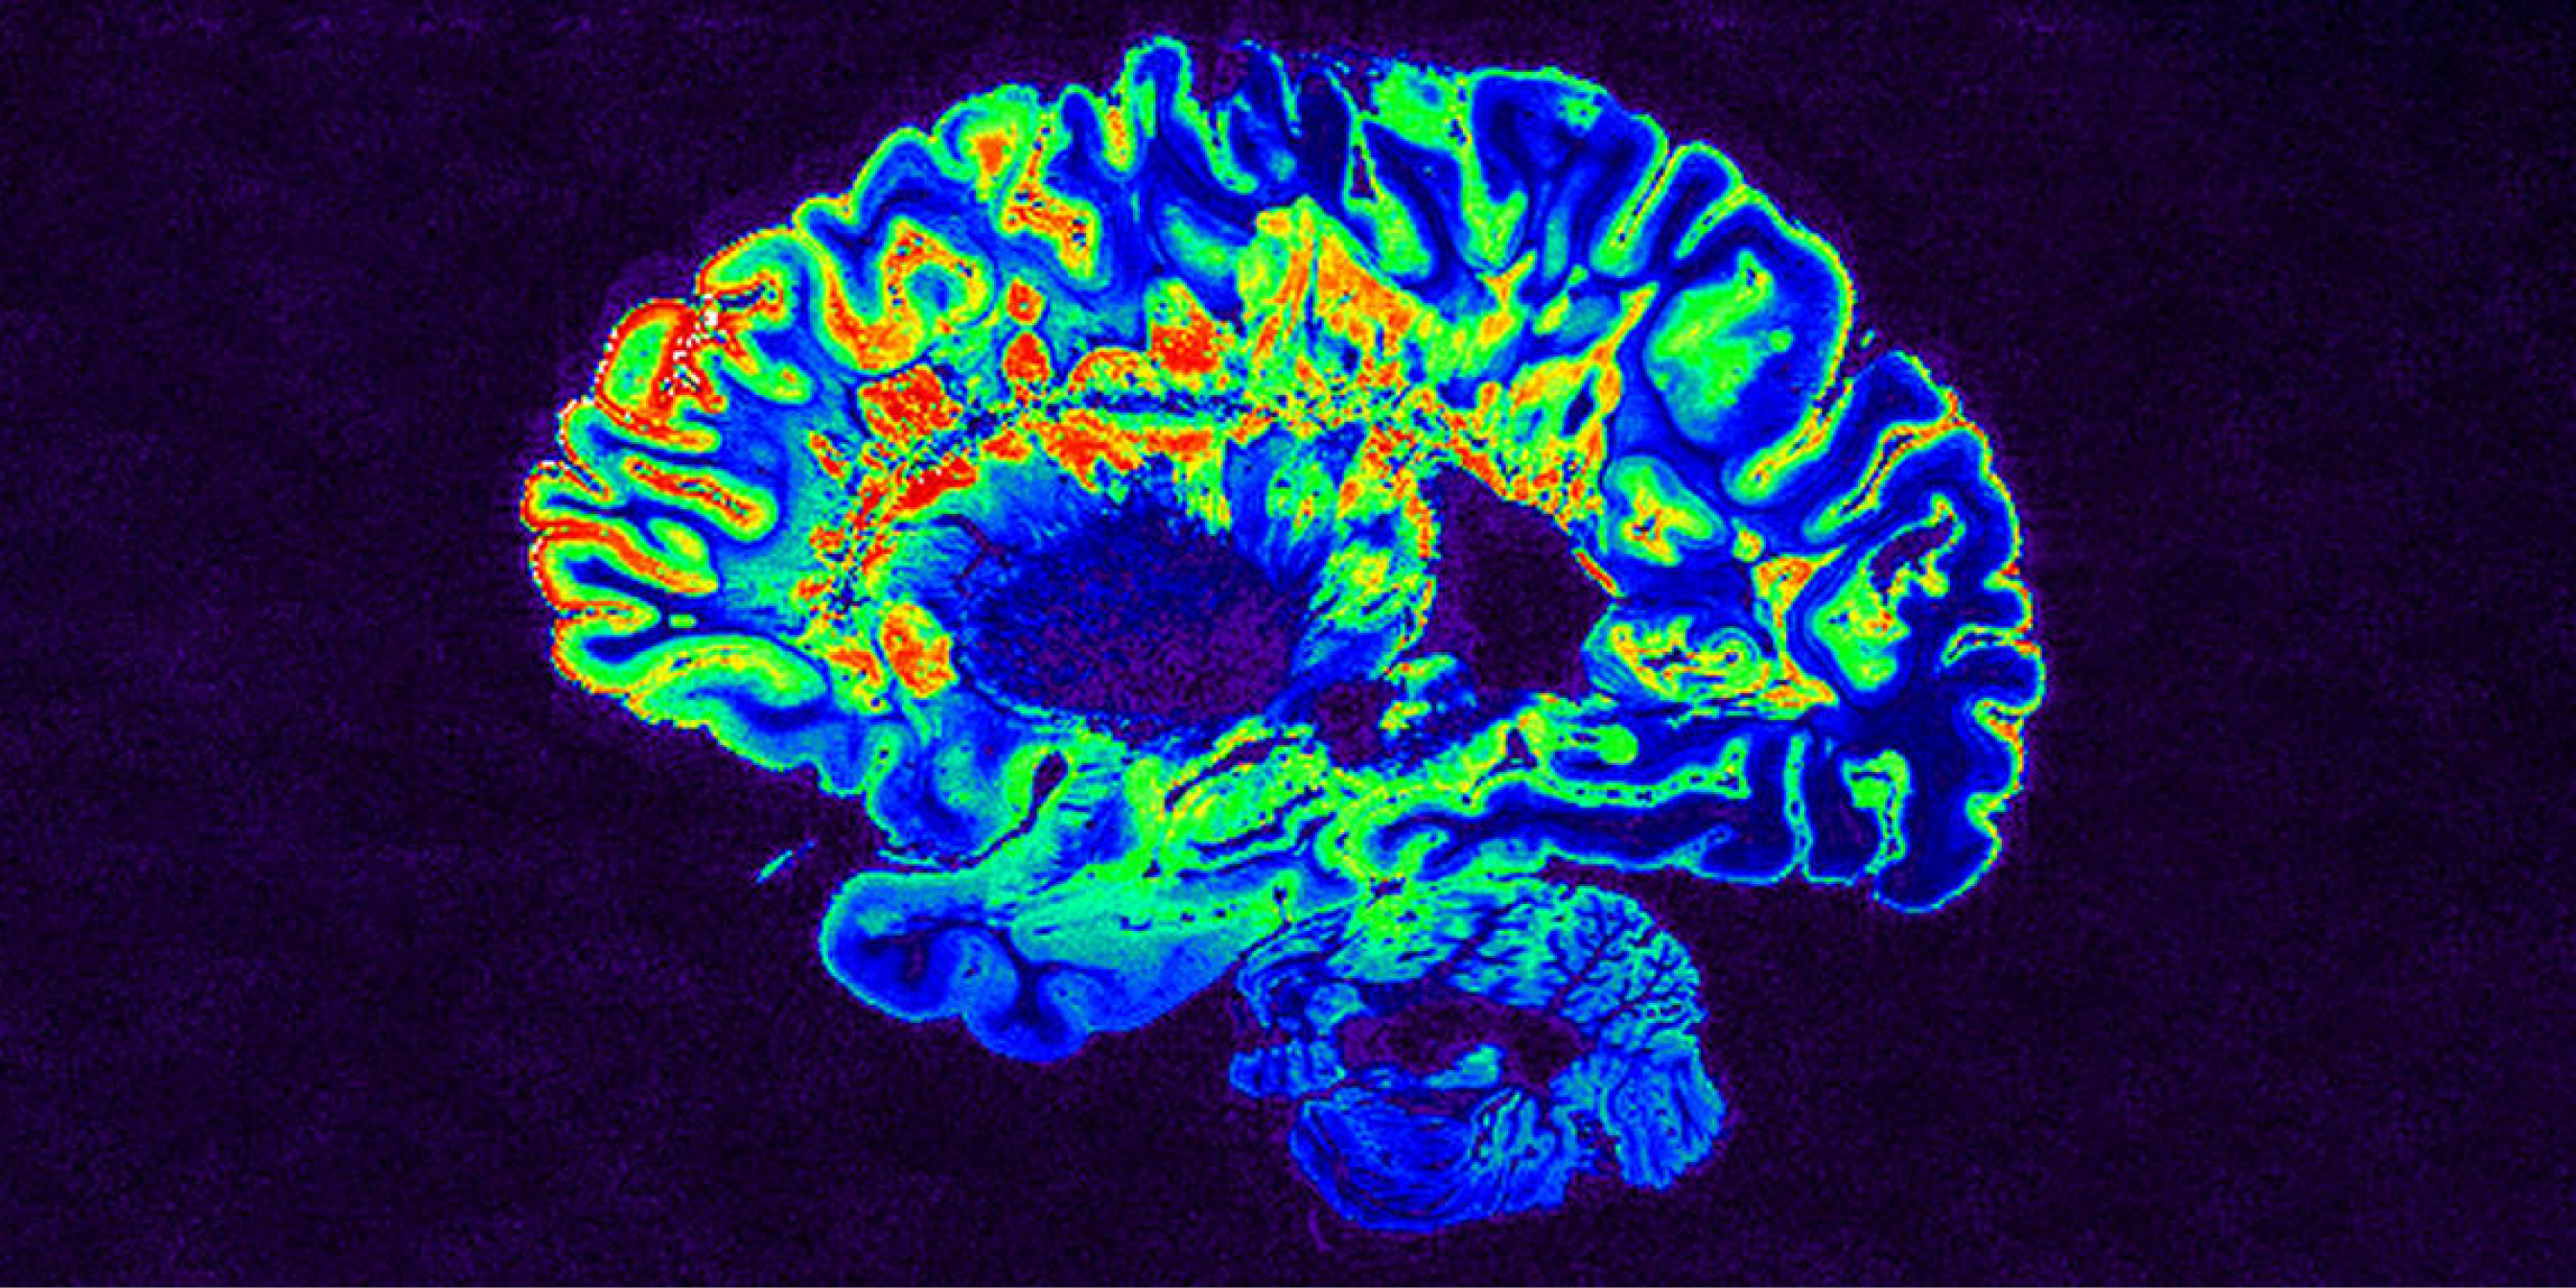

Diagnosing multiple sclerosis with artificial intelligence

Multiple sclerosis (MS) is an autoimmune disease of the central nervous system (the brain and spinal cord). World MS Day 2022 was held on May 30. To d...